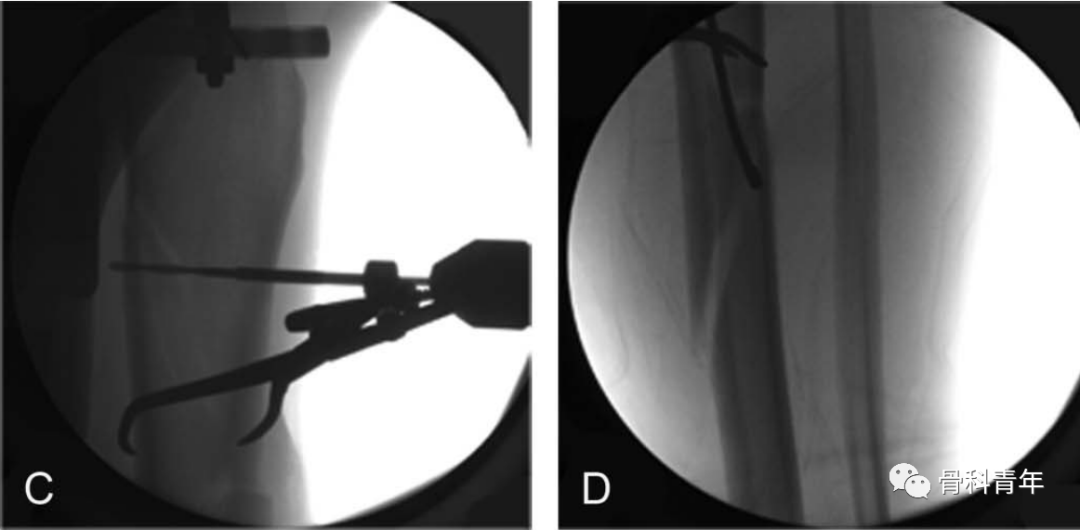

通过在胫骨平台下方1cm,平台偏后部置入一根钢丝,另一根钢丝置入踝关节软骨下骨处,钢丝连接外侧2/3碳纤维环形架,施加110kg拉力形成张力。由于钢丝非中心置入,因此在轴向撑开时,骨折断端可能会向后成角,需要在中部后方垫消毒巾,并巾钳固定。

该外架为碳纤维,术中不影响透视,且该2/3外架,将连接杆置于小腿后方,给髓内钉的内外置钉留出空间。